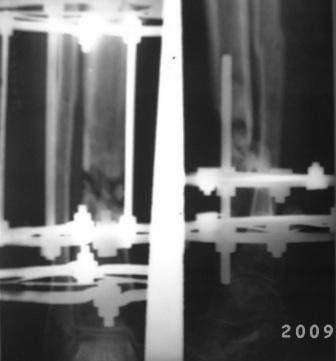

Уважаемые коллеги. Обратился б-ной 39лет, ДТП 8-мес назад, о/оскольчатый перелом костей правой голени, в ЦРБ произведена ПХО раны, остеосинтез спицами и проволкой, гипсовая повязка, со слов б-ного рана зажило первично, гипсовая повязка переложена несколько раз, но сращения не наступило, 2 мес назад КДО аппаратом Илизарова, срашения нет, после обратился к нам. Локально: признаков воспаления, лимфостаза нет, п/о рубец небольшой, сгибательная контрактура г/с сустава. Р-снимки прилагаются. Наш план.1. Перемонтаж аппарата, устранение смещения, остеотомия в/з б/берцовой кости с постепенным низведением до полной компрессии в обл ложного сустава. 2. БИОС с рассверливанием к/м канала. Уважаемые коллеги, помогите советом! Можеть быть сначала резекция концов л/с и потом низведение. или костная пластика? Или после завершения удлинения через какое время рекомендуется БИОС? С уважением Абдурашид.

Хотелось бы увидеть снимки голени на протяжении, и, если можно, с более высоким качеством. Неплохо бы сделать сравнительные снимки для сопоставления со здоровой голенью. По представленным картинкам очень трудно оценить состояние концов отломков и величину дефекта.

Если нет инфекции, то резекция выглядит избыточной. Костная пластика не нужна, если в перспективе закрытый интерамедууллярный остеосинтез.

Если дефект сейчас больше 2 см, то можно сделать сегментарный "транспорт", т.е. после кортикотомии и дистракции в верхней трети добиться хотя бы частичного контакта основных отломков на уровне

несращения. Если концы отломков и промежуточные отломки жизнеспособны, а дефект небольшой, то можно просто заштифтовать.